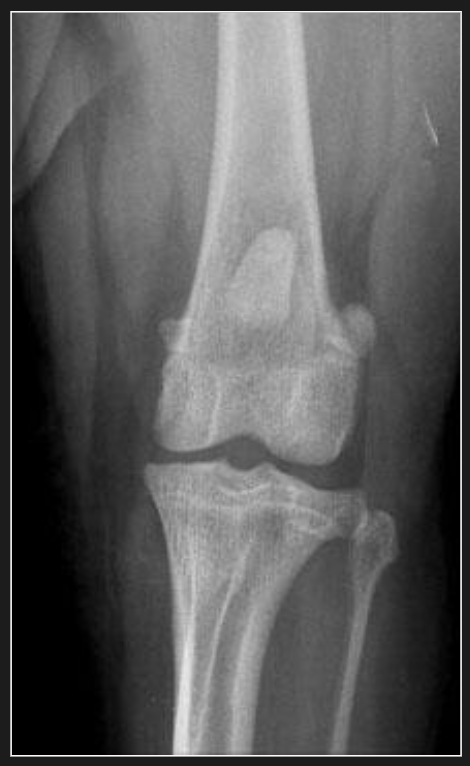

Vue crânio-caudale

Positionnement Crânio-caudale :

- L’animal est couché en position dorsale.

- Étirer le membre en effectuant une bonne traction et rotation interne sur la patte.

- S’assurer d’avoir le bassin bien droit et apposé à la table.

- S’assurer d’avoir le tibia bien droit et parallèle à la table.

- S’assurer d’avoir les rotules bien centrées.

Collimation :

- Distalement, la collimation doit inclure le tiers proximal du tibia.

- Proximalement, elle doit se rendre jusqu’au tiers distal du fémur.

- N’inclure que la largeur de la patte avec le marqueur sans trop d’espace vide.

Centrage :

- Centrer le faisceau sur le genou.

Orientation :

- Avant d’envoyer les radiographies, il est important de s’assurer que la droite du membre est à gauche et que sa gauche à droite sur l’écran.

- Également, l’extrémité distale du membre doit pointer vers le bas de l’écran.

Mesure :

- Une fois l’animal en position radiographique, placer la règle au niveau du genou afin de prendre une mesure.